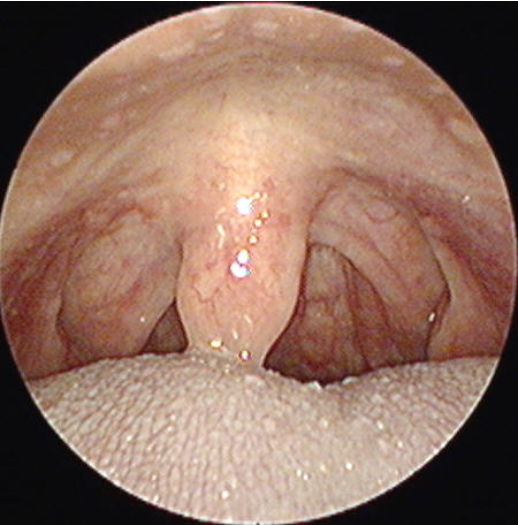

편도염증상, 편도염증상, 편도염두통, 편도염열 급성 편도염증상으로는 인후통이 심하고 두통, 근육통, 연하장애가 발생하여 발열과 함께 오한증상이 나타날 수 있으며 권태감 등의 편도염증상(편도염증상)이 일주일 이상 지속됩니다. 목을 촉진한 경우 부어 있는 림프절이 만져지고, 만져진 림프절에서는 통증을 호소합니다. 입을 벌리고 입천장 안을 볼 때 붉은 발적과 부종을 관찰할 수 있습니다. 만성 편도염의 증상은 인후통이 있지만 열이 없는 것이 특징입니다.